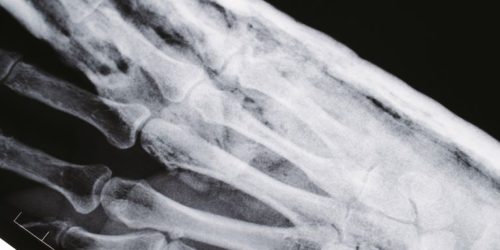

東京の一角には、歴史と現代が共存する魅力的なエリアが広がっている。その中でも特に注目されるのが、利便性の高い交通網と多彩な施設を整えた一地区である。このエリアには商業施設や飲食店が点在し、ビジネスマンや観光客で賑わう一方で、地域住民の生活を支える様々な医療機関も存在している。この地域には、内科を専門とする医療機関がいくつかあり、地域の健康を支える重要な役割を果たしている。内科は一般的に、身体の内面的な問題、例えば消化器系、循環器系、呼吸器系などの問題を把握し、診断、治療、予防を行う分野である。

戦後、国民の健康を盾にした医療体制の整備が進む中で、内科の役割はますます重要となり、地域に根ざしたクリニックや病院が増えた。このエリアにおける内科の医療機関は、地域住民が安心して利用できるよう、アットホームな雰囲気を大切にしているところが多い。診察室は明るく清潔感があり、看護師や医師は優しい態度で患者に接する。こうした環境作りは、患者にリラックスしてもらい、より良い治療結果を得るために欠かせない要素とされている。内科では風邪やインフルエンザなどの一般的な疾患の治療だけでなく、慢性疾患如き高血圧、糖尿病、高コレステロールなどの管理や、定期検診に基づく健康診断も行われる。